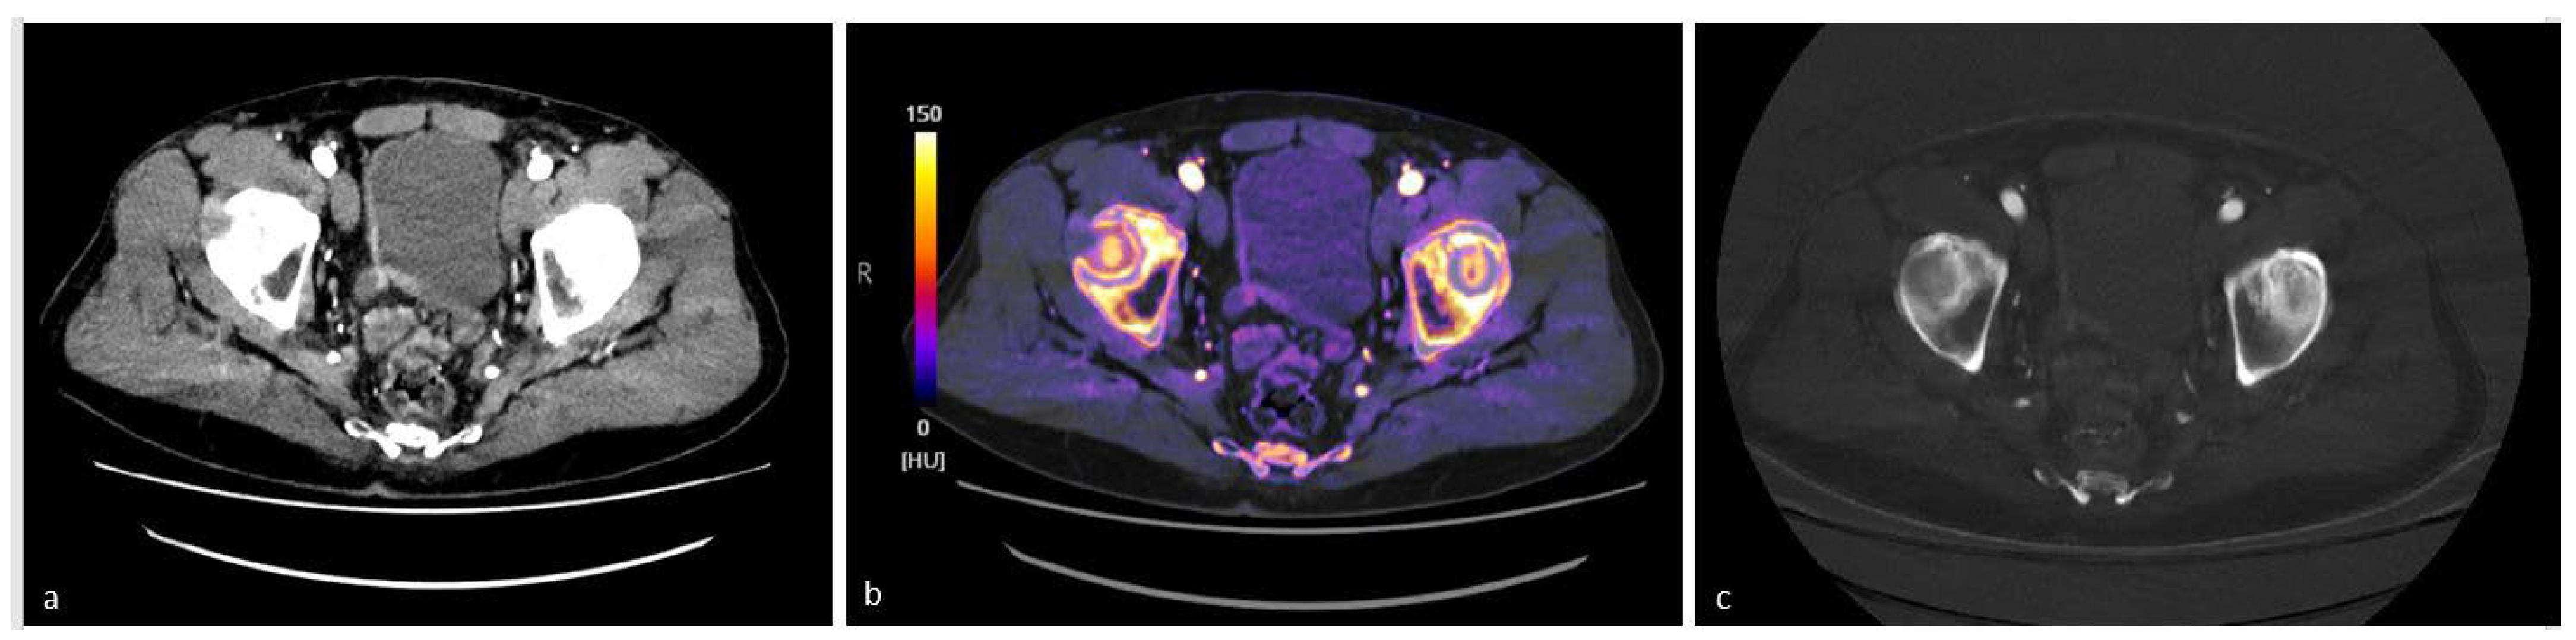

4.1. Characterization of Urinary Stones